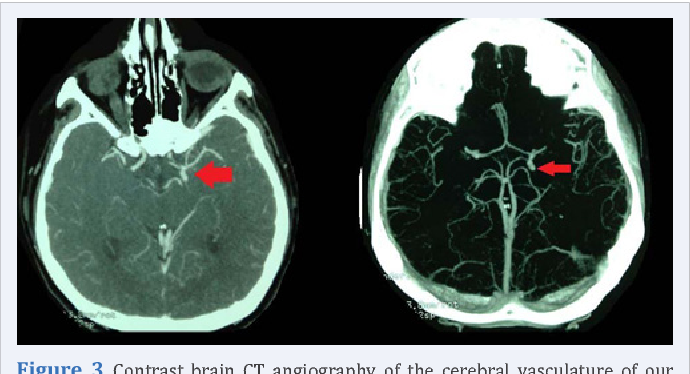

Berry aneurysm refers to dilated portion of blood vessel in Circle of Willis. It is an intracranial aneurysm. Berry aneurysm is the most common cause of subarachnoid hemorrhage. The attached image demonstrates the berry aneurysm on CT angiogram. Reference: https://radiopaedia.org/articles/saccular-cerebral-aneurysm Image via: https://www.semanticscholar.org/paper/Intracranial-Congenital-Berry%27s-Aneurysm%2C-Recurrent-Amin-Shukir/151d38d46608c10802cb33f540d216386f0fa16c/figure/2